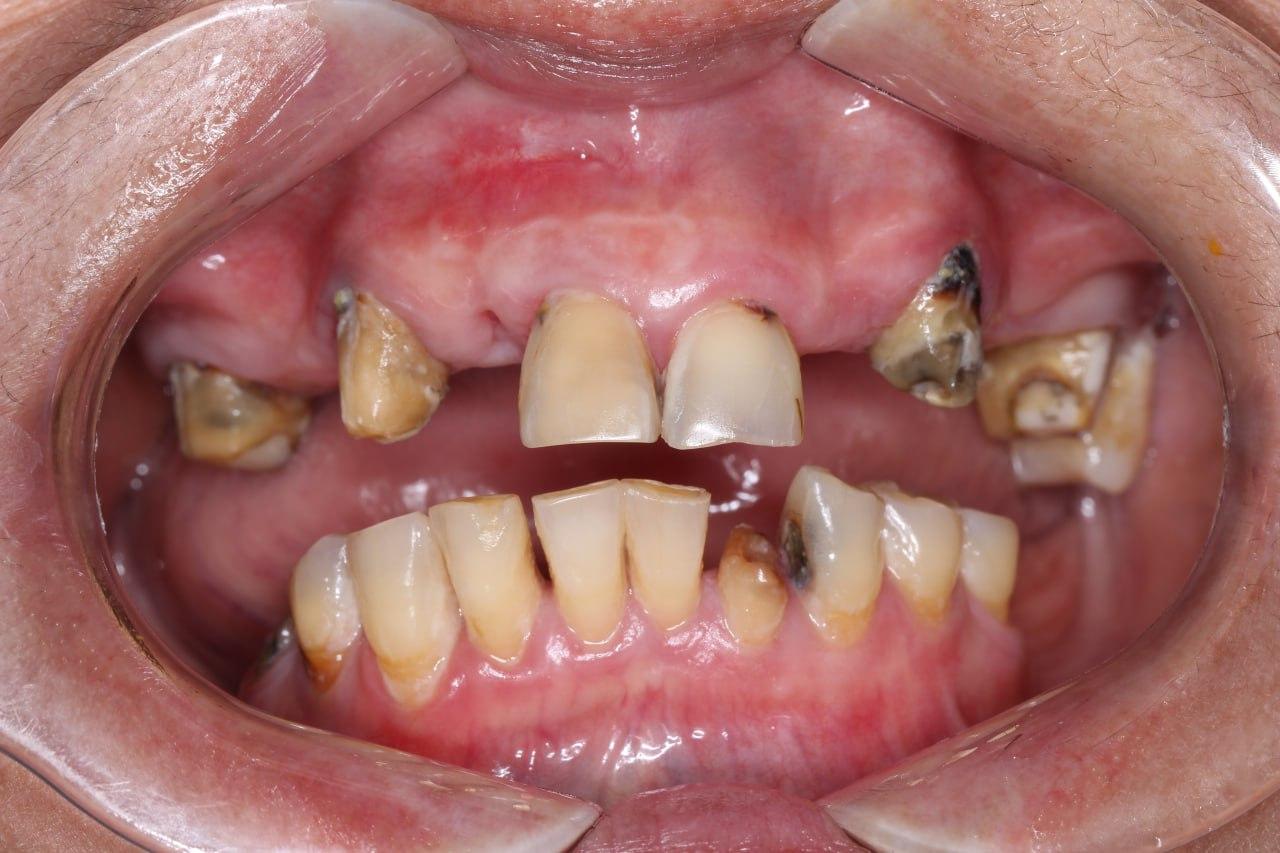

before

after